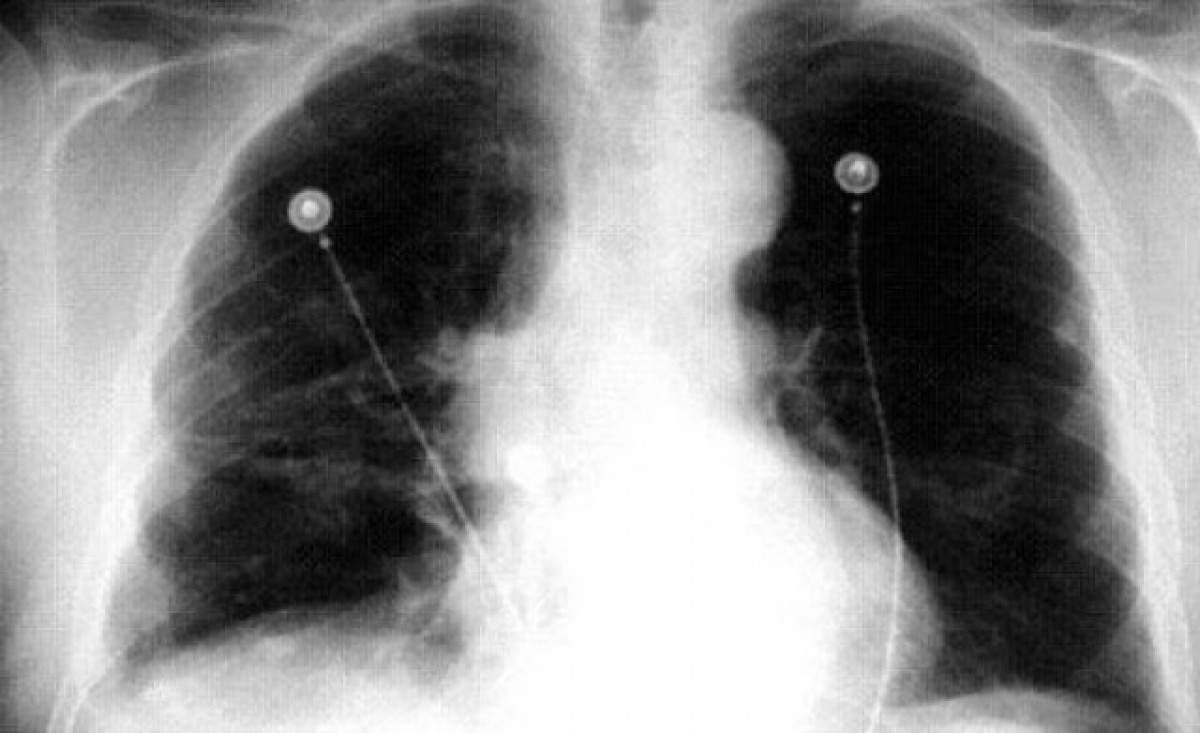

Segons expliquen des ICAPEM, el càncer de pulmó és el quart tumor amb més incidència entre les dones espanyoles, amb un augment en la mortalitat del 6 per cent anual i més de 5.000 casos nous a l'any. A Europa, la mortalitat per càncer de pulmó entre les dones és equiparable a la mortalitat per càncer de mama. "No obstant això, encara hi ha la percepció entre la població que és una neoplàsia gènere-dependent i lligada al sexe masculí", apunten.

La previsions de l'Agència Internacional d'Investigació en Càncer (IARC, per les sigles en anglès), dependent de l'Organització Mundial de la Salut (OMS), alerten de l'increment de casos de càncer de pulmó d'aquí a l'any 2040. A Espanya, concretament, podrien augmentar els 6.914 casos que s'estimen per a l'any 2018 a més de 8.600 en 2040.